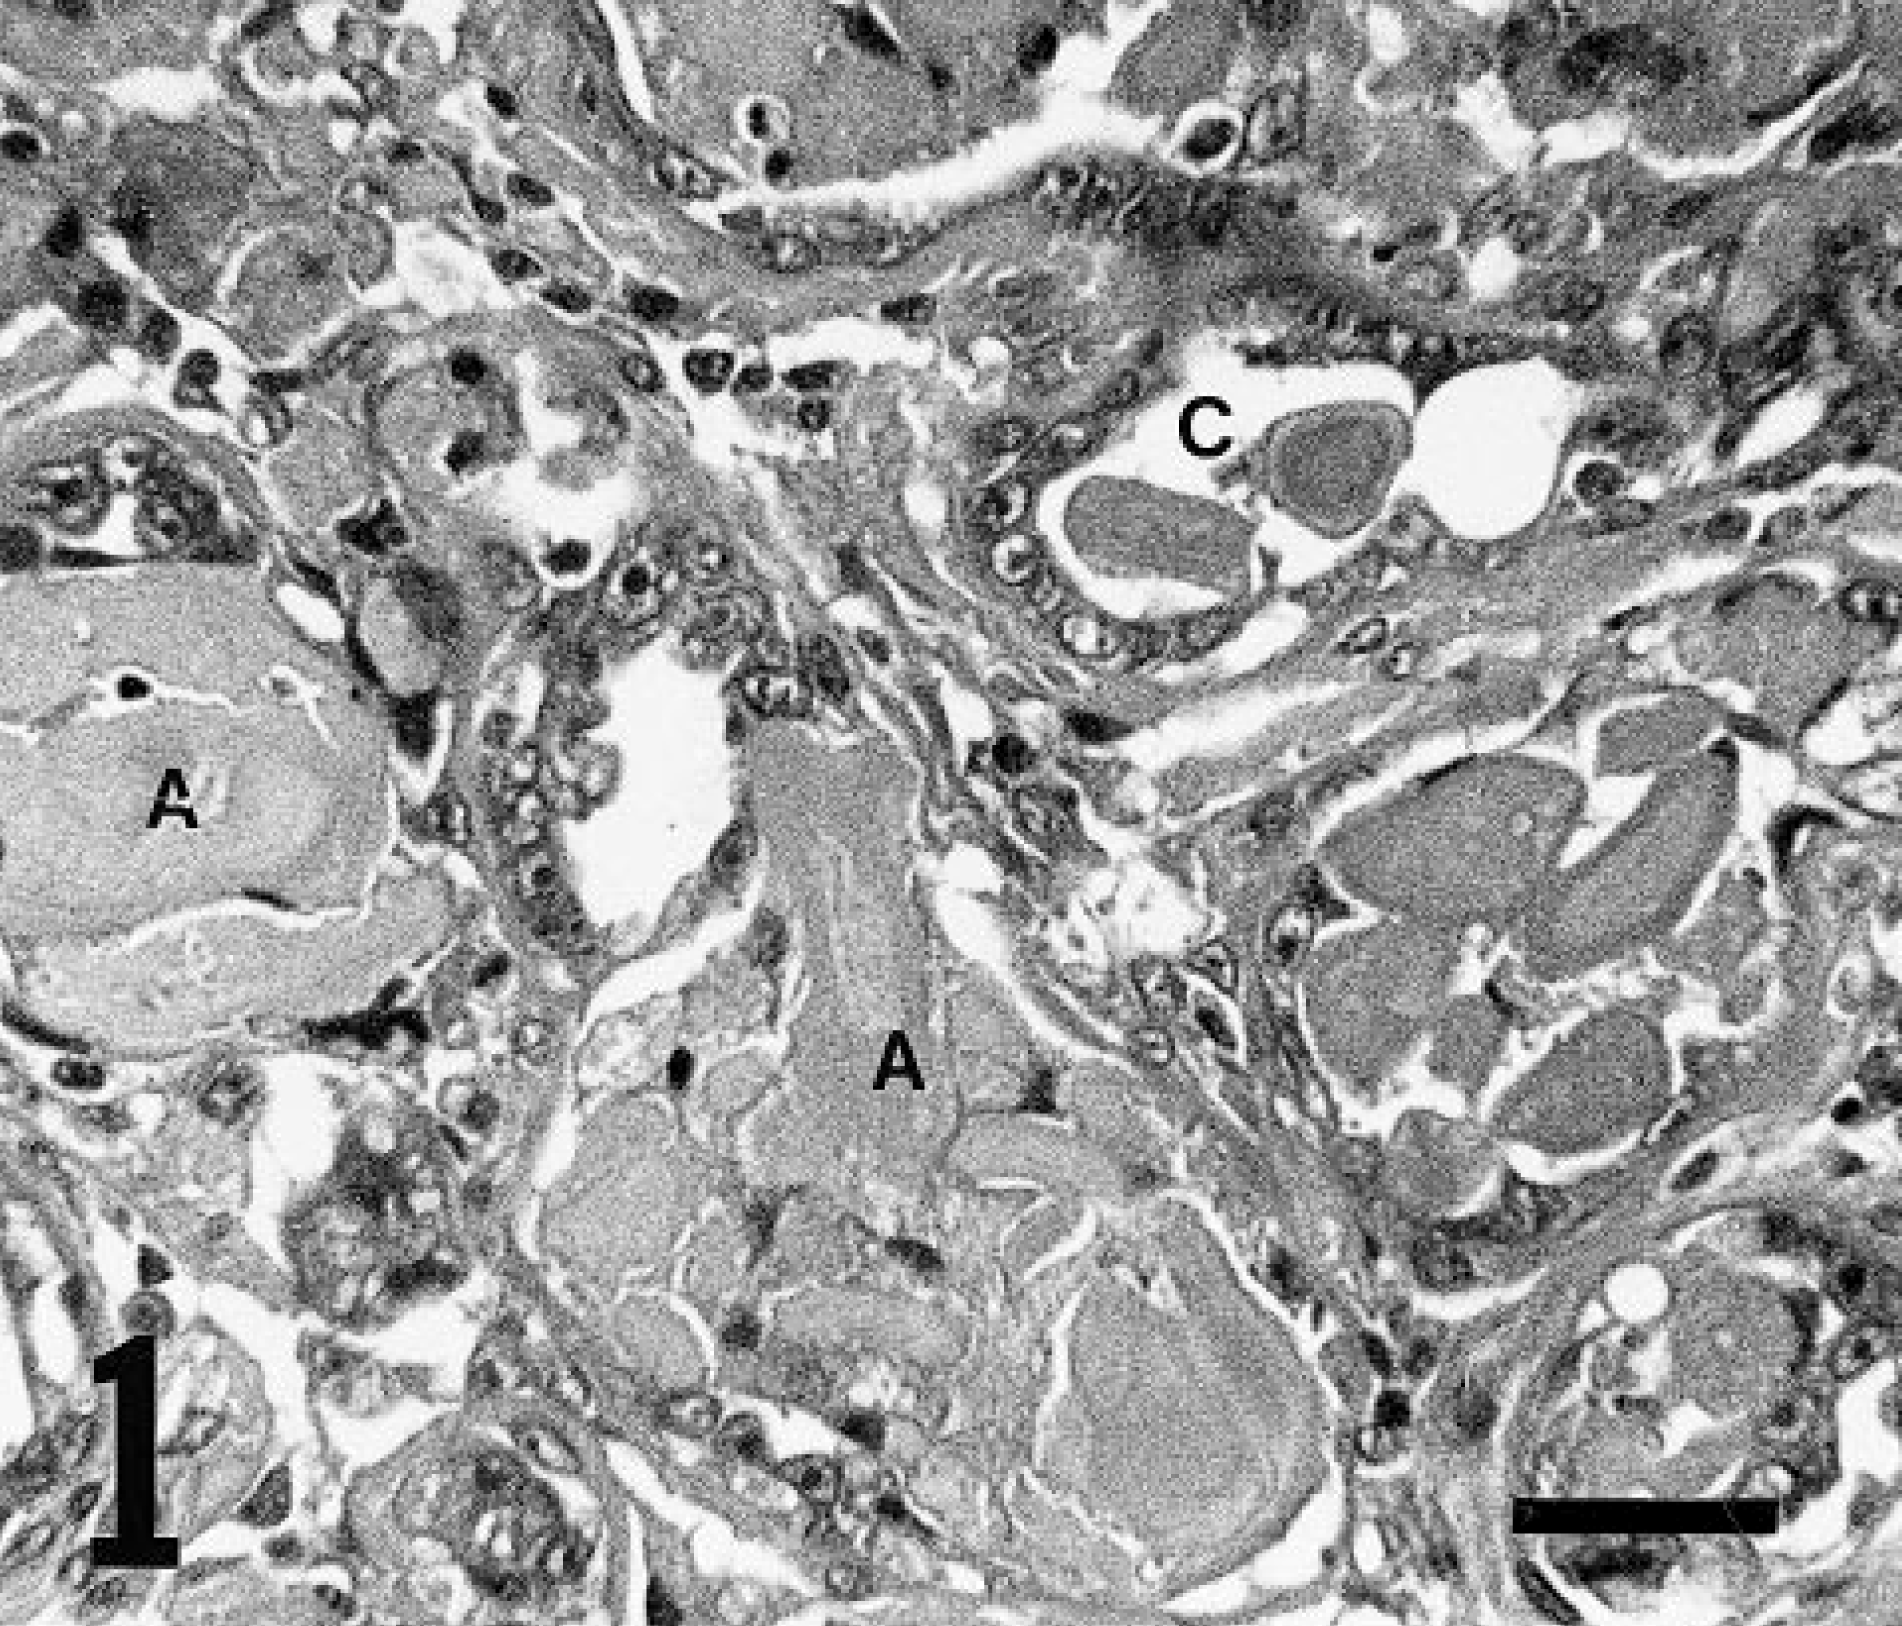

The adenoma of dog No. 1 consisted of a well-demarcated proliferation of well-differentiated cuboidal or columnar epithelium in an acinar or lobular pattern. In some areas, an acellular amorphous pale eosinophilic material (amyloid) was seen in the lumina of the acini lined by neoplastic cells and in the stroma of the tumors (Fig. 1). Concentrically laminated pale eosinophilic bodies (corpora amylacea) were found in the lumina of the acini.

Mammary adenoma; dog No. 1. Adenoma consists of a well-demarcated proliferation of well-differentiated cuboidal or columnar epithelium in an acinar pattern. An acellular amorphous pale eosinophilic material (A) is seen in the lumina of the neoplastic acini and stroma of the tumors. Corpora amylacea (C) are found in lumina of the acini. HE. Bar = 30 μm.